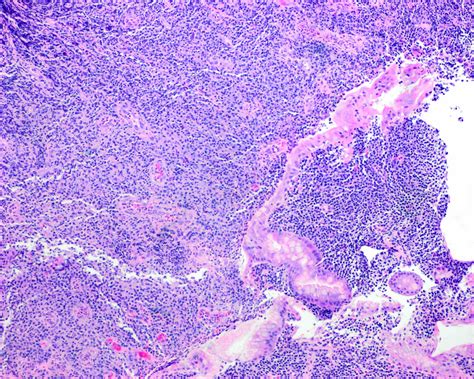

• Histopathological Examination: The biopsy samples are examined under a microscope to confirm the presence of MALT lymphoma cells. Immunohistochemical staining and molecular tests may also be performed to further characterize the cancer cells.